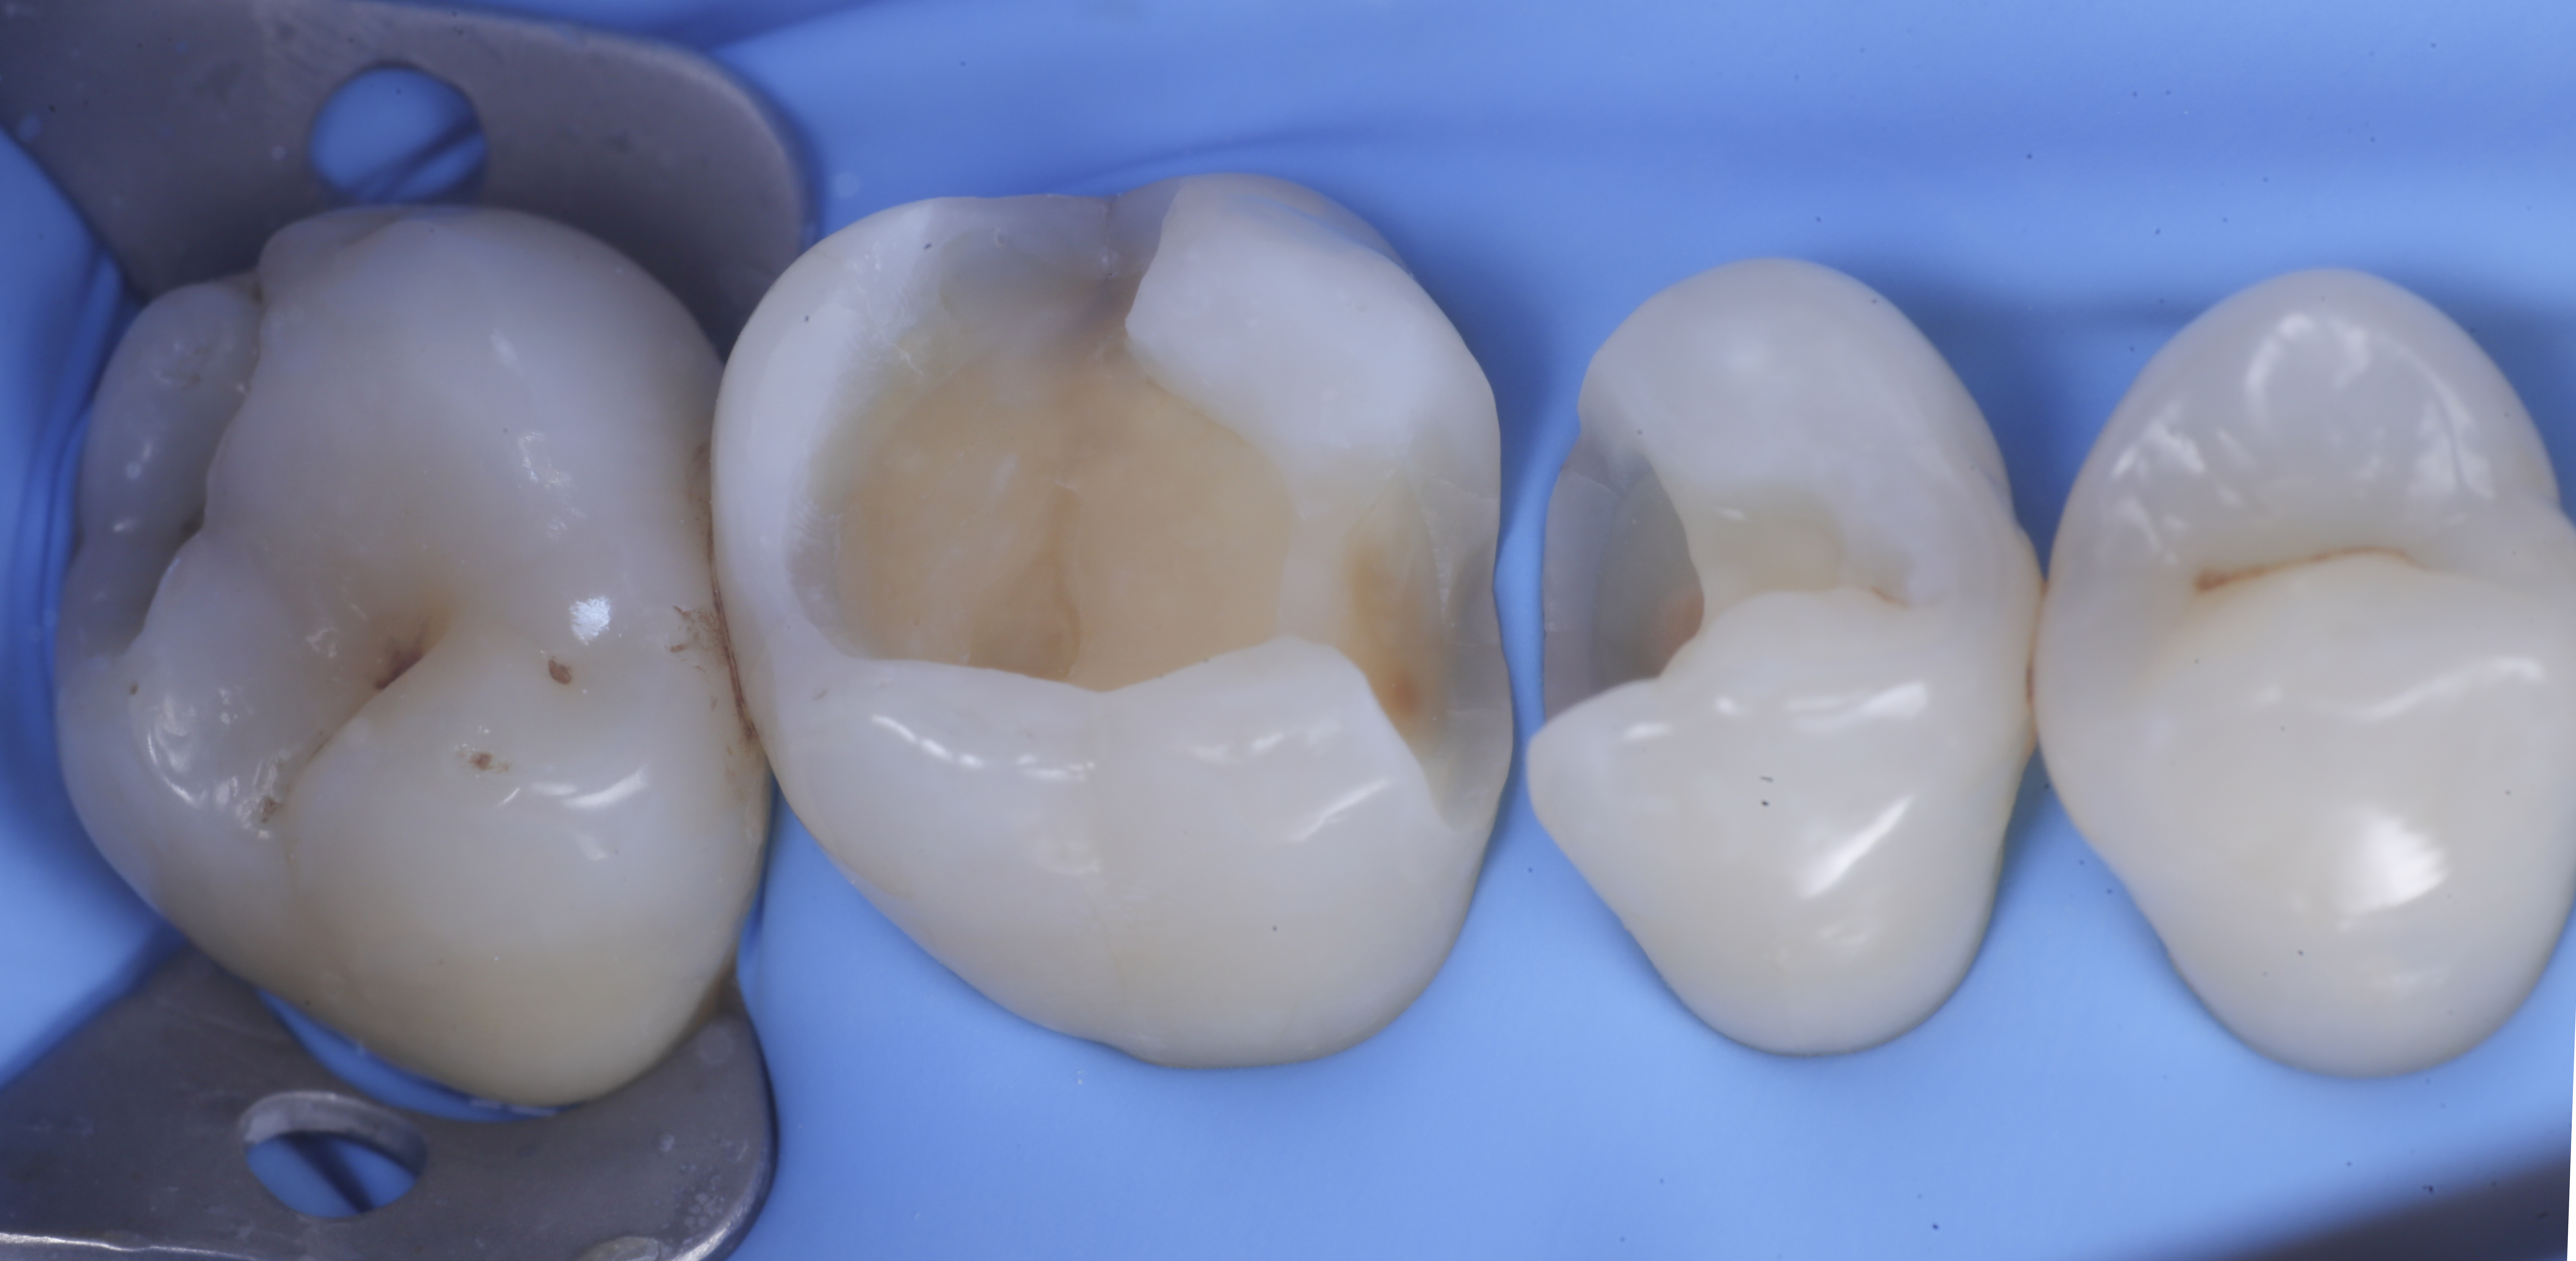

foto 2 Isolamento e aspetto delle cavità ultimate

foto 3 Aspetto vestibolare della cavità ultimate

foto 4 Aspetto della chiusura cervicale e sulle pareti assiali dato dalla prima matrice

foto 5 Aspetto della chiusura cervicale e sulle pareti assiali della seconda matrice